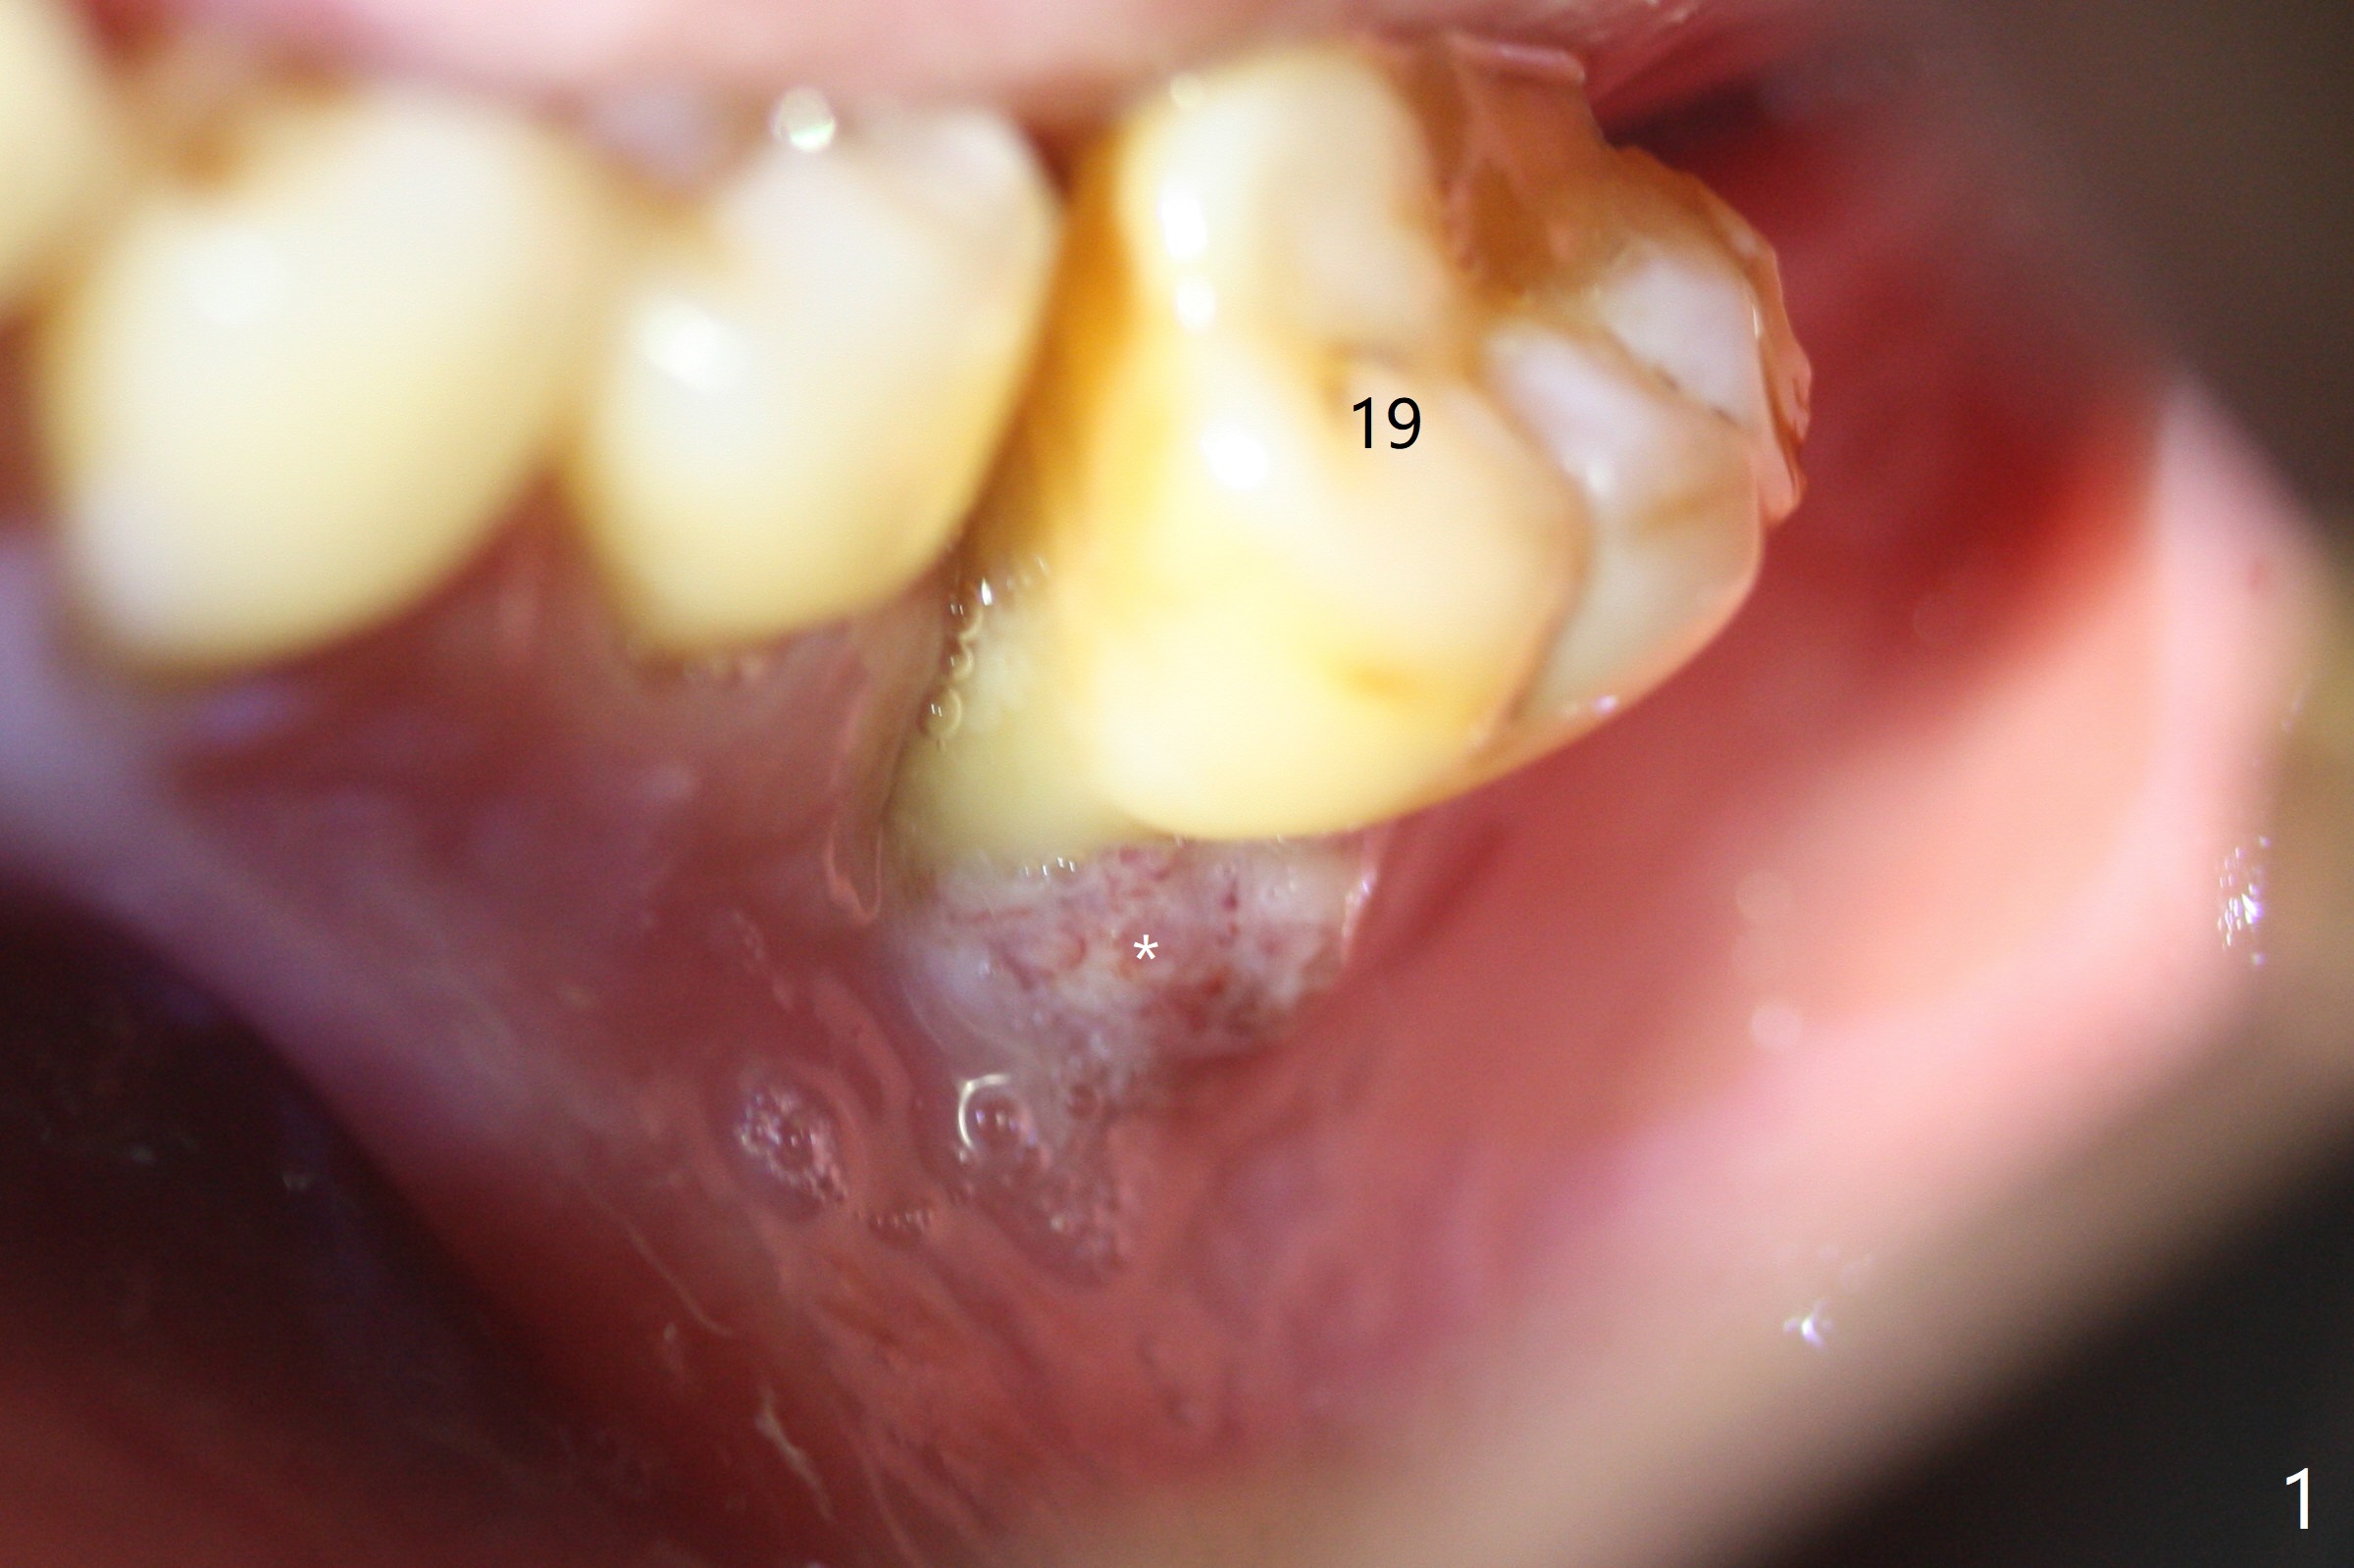

A 50-year-old man (smoker, bruxer (also missing the tooth #2 and 3)) requests extraction of the tooth #19 with mobility and buccal gingival infection (Fig.1 *). There is severe bone loss around the mesial root (Fig.2 M). It appears that the soft tissue (Fig.3 *) prevents the bone graft from being deposited in the distal surface of the neighboring root.